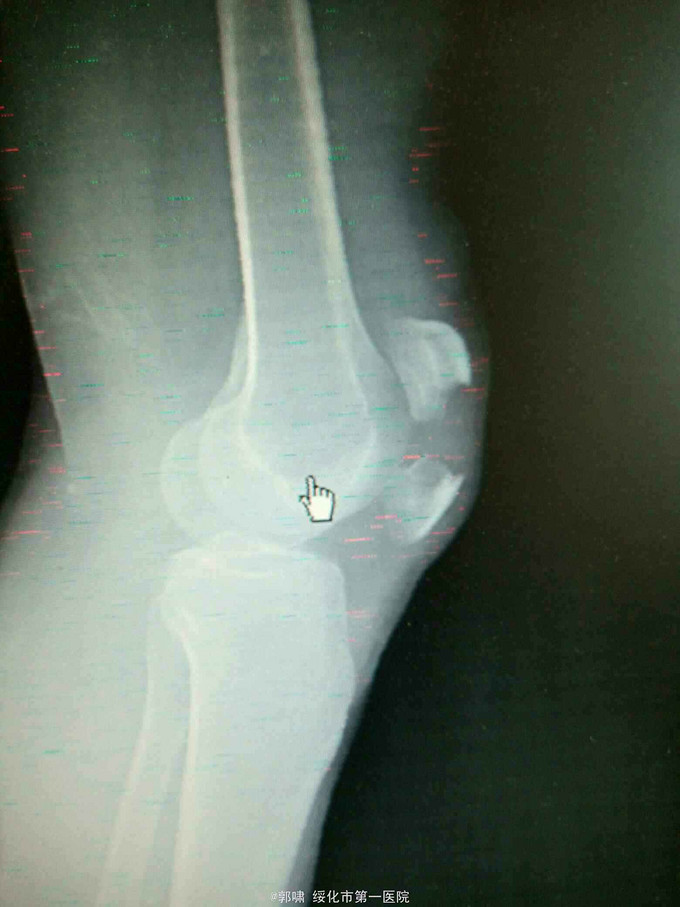

诊断:左髌骨骨折。立即予以腰麻下行切开复位内固定术。术中复位骨折,缝合筋膜,冰水浸泡髌骨爪约10分钟。待髌骨爪变软。选取合适大小的髌骨爪。应用记忆合金髌骨爪内固定。立即用40°温盐水热敷局部。使记忆合金加速抓紧。环抱。缝合爪齿二道,防止脱落。缝合关节囊,韧带组织。术毕。

应用记忆合金髌骨爪内固定髌骨骨折。手术时间基本在20----30分钟内都可以完成。局部损伤小。固定牢靠,确实。患者二个月就可以下地负重活动。具体手术技巧。一是髌骨爪提前用冰盐水侵泡10分钟左右。待记忆合金变软即可使用。二。固定牢靠后立即用40°温盐水热敷。使其快速抓紧。三,缝合爪齿,防脱。四如有粉碎,小的骨块可以缝合筋膜固定。有大骨块,最好环扎钢丝,或穿针固定,有时穿骨隧道钢丝捆扎。效果也不错。只要做到以上几点。安全无忧了!以下是以前做的片子。可以看一看。